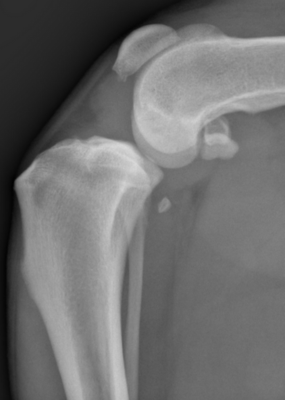

Diagnostic

Le vétérinaire combine plusieurs examens :

- Examen orthopédique spécialisé (test du tiroir) pour détecter la laxité articulaire

- Radiographies pour visualiser anomalies osseuses et arthrose

- Arthroscopie si nécessaire pour confirmer la rupture de ligaments croisés et d’éventuelles les lésions méniscales